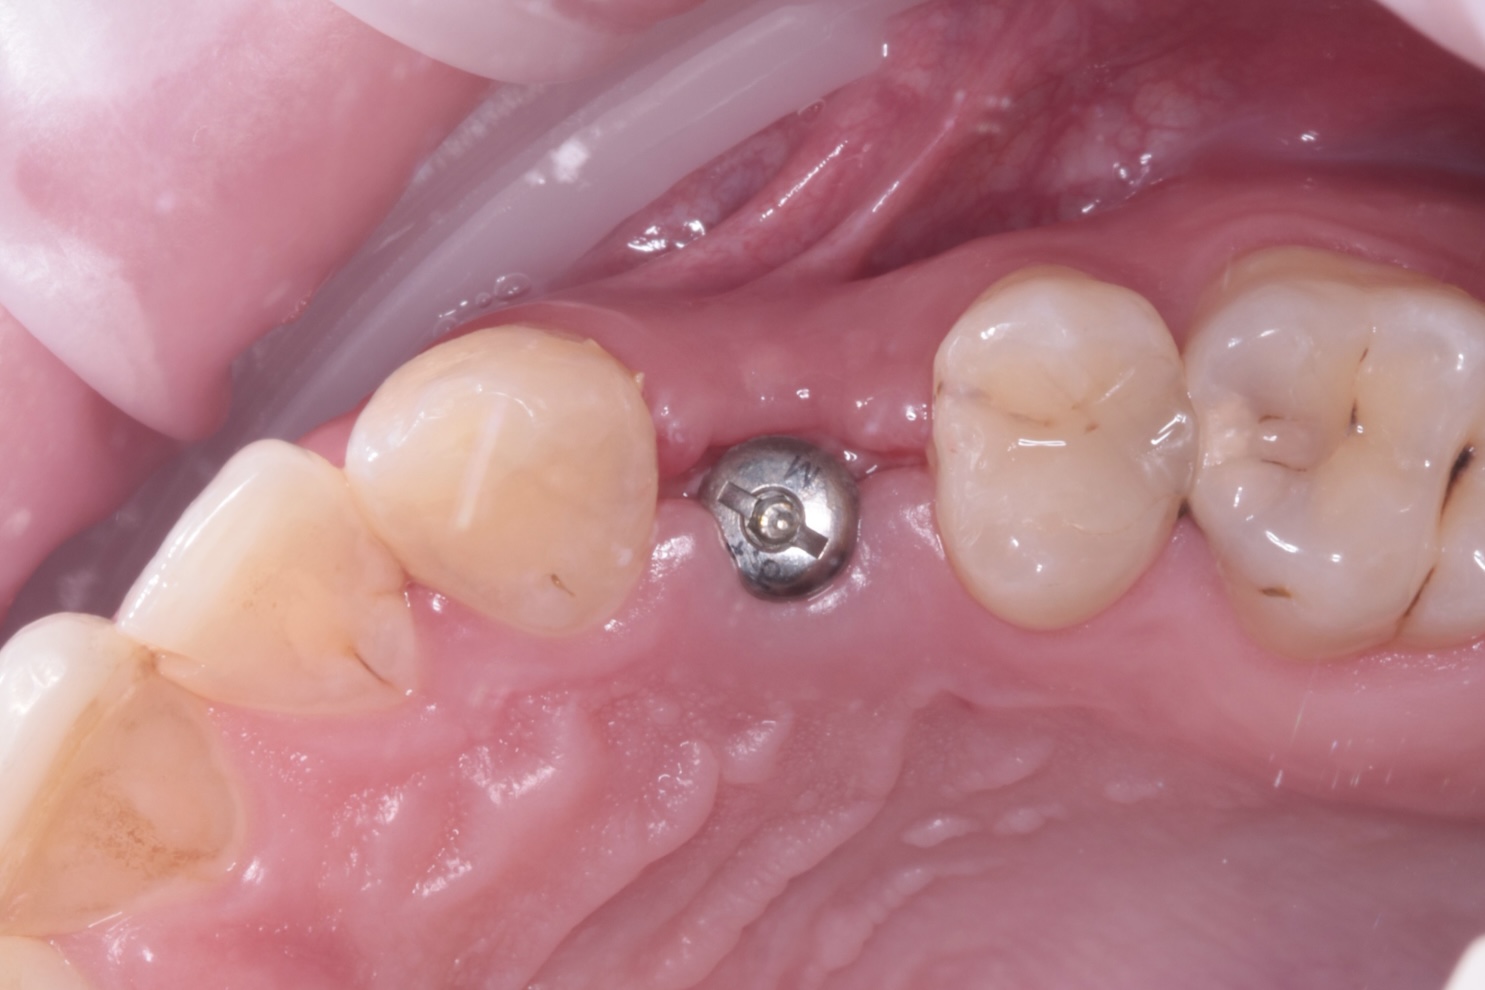

Наши работы